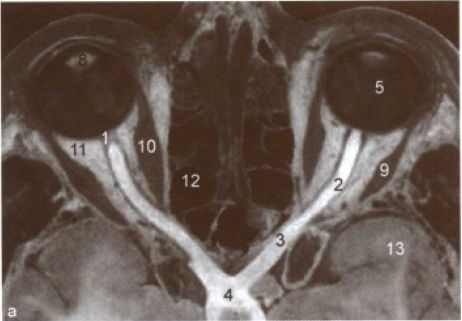

我们先来说一下视神经和视盘。请看图1。视神经是位于视网膜神经节细胞的轴突汇聚成束,从视盘处穿出眼球,先后在眼框、视神经管、颅内走行,然后在垂体上方两侧视神经交叉形成视交叉。医生可以直接在人体观察到的是视神经在眼球内的起始的那一段,称为“视盘”,也称“视乳头”。当然也要借助眼底镜检查。正常视盘的表现见图2。边界清楚,颜色呈淡红色。正常情况下,视盘上有丰富的毛细血管,而且神经纤维束是透明的,光线到达时,可以通过光的折射使视盘呈现出淡红色。